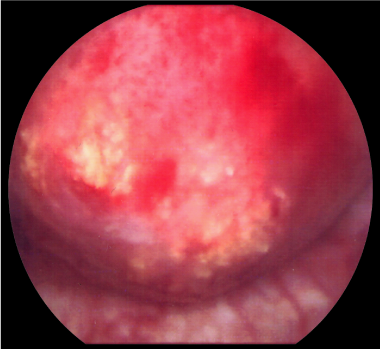

A 70-year-old Caucasian man presented with a three day history of painless gross haematuria associated with storage lower urinary tract symptoms. He is a non-smoker with no family history of bladder cancer. He has a past history of squamous cell carcinoma of the temple, basal cell carcinoma of the eyebrows, plantar fasciitis, rosacea and solar keratosis. Clinical examination was unremarkable. Mid stream urine microscopy and culture confirmed microscopic haematuria and no significant bacterial growth. Urine cytology showed no malignant cells. He had normal PSA, liver function tests, renal function tests, clotting profile and FBC. Ultrasound scan of the kidneys, ureters and bladder showed a 2cm echogenic bladder lesion in the right lateral bladder wall (Figure 1). Cystoscopy showed a 2cm calcified bladder lesion on the posterior wall with another 0.5cm lesion above the trigone (Figure 2). The appearance was highly suspicious of a solid bladder tumor or bladder schistosomiasis. Trans-urethral resection of these two bladder lesions was performed with deep resection. Complete resection was achieved in the smaller lesion but not in the larger lesion due to the density of the calcifications. Bimanual examination under anaesthesia before and after the bladder lesion resection showed no bladder wall thickness or palpable bladder mass. Histology of the resected bladder lesion ruled out bladder malignancy and demonstrated a degenerative eosinophilic material with extensive ossification and accompanying foreign body giant cell reaction in keeping with bladder amyloidosis (Figure 3).

Figure 1 Bladder ultrasound scan showing echogenic filling defect on the posterior aspect of the bladder.